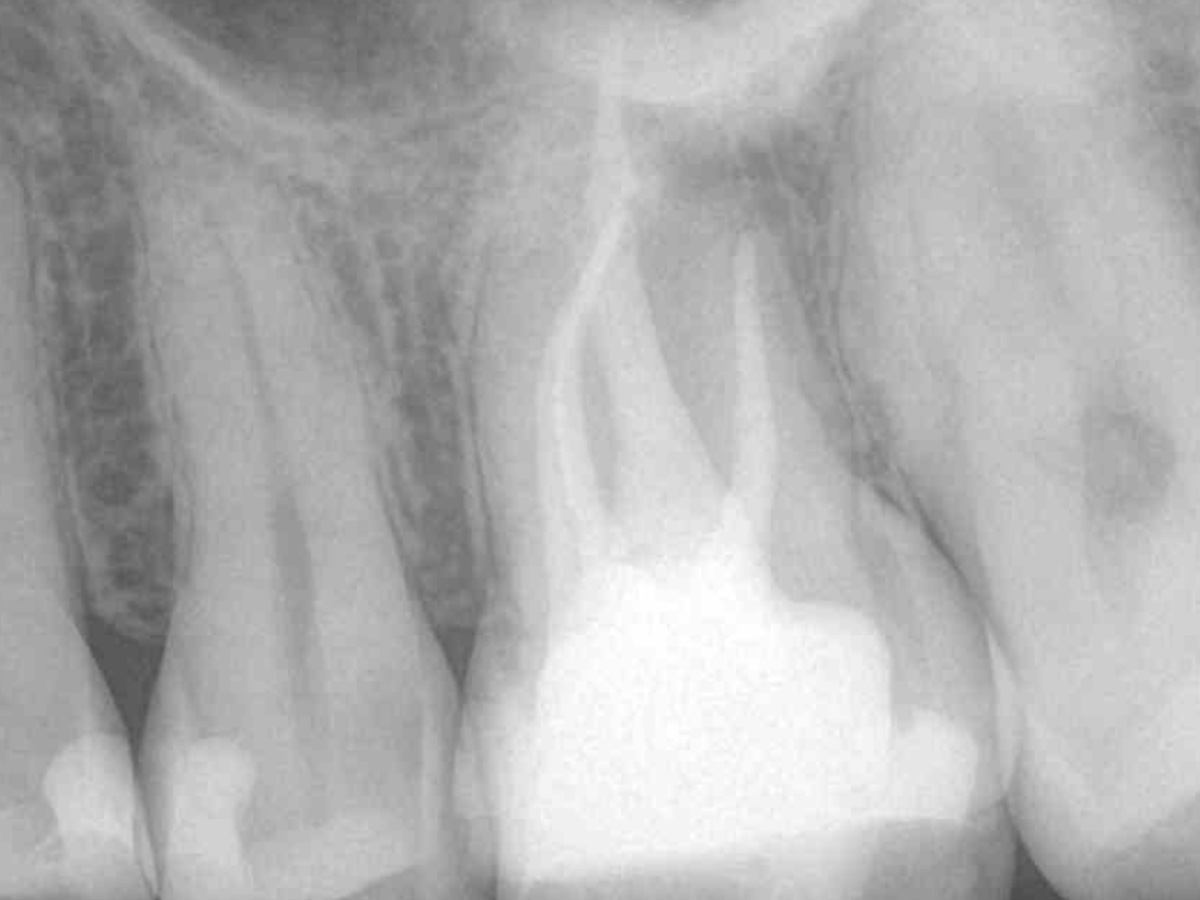

Obturation nach einer erfolgreichen Revision der insuffizienten Wurzelkanalfüllung mit einer symptomatischen apikalen Parodontitis

Der Patient stellte sich mit Aufbissschmerzen vor, wobei die klinische und röntgenologische Untersuchung eine symptomatische apikale Parodontitis an einem bereits wurzelkanalbehandelten Zahn 26 ergab. Die DVT-Aufnahme deutete auf einen unbehandelten zusätzlichen Kanal in der mesio-bukkalen Wurzel hin. Die Darstellung und Behandlung des mb2s sowie die Revision der bereits behandelten Kanäle erfolgte mit dem XP-endo® Rise Shaper bei einer hohen Umdrehungszahl von 2.500rpm.

Abbildung 1

DVT axial